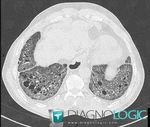

ILD = interstitial lung disease = pneumopathies interstitielles

Groupe large et hétérogène de maladies pulmonaires

avec en commun :

« dyspnée, toux, infiltrats bilatéraux sur CT ou Rx »

-idiopathiques : Idiopathic Interstitial Pneumonia (IIP)

-granulomateuse : sarcoïdose…

-secondaires : médicaments, maladies systémiques

-autres : histiocytoses pulmonaires, …

Important de reconnaître une ILD secondaire à connectivite

car le traitement est différent et le pronostic est meilleur (vs idiopathique)